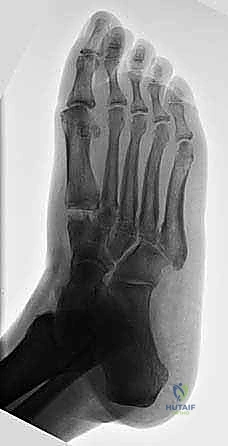

- الأشعة السينية أثناء الوقوف (Weight-bearing X-rays): وهي أهم أداة تشخيصية. الأشعة العادية والسرير فارغ لا تظهر المشكلة الحقيقية؛ يجب التقاط الأشعة والمريض يقف ليتحمل وزن الجسم، مما يظهر الانهيار الفعلي للمفاصل وتضيق المسافات بين العظام.

لفهم أهمية جراحة تثبيت مفصل منتصف القدم، يجب أولاً أن نفهم التشريح الفريد لهذه المنطقة. يتكون منتصف القدم (Midfoot) من مجموعة من العظام الصغيرة التي تتشابك معاً لتشكيل قوس القدم (Foot Arch). هذه العظام تشمل:

تعمل هذه العظام معاً كـ "ممتص للصدمات" أثناء المشي والجري. المفاصل التي تربط هذه العظام (مثل مفصل تارصو-ميتاتارسال أو مفصل ليزفرانك Lisfranc joint) هي مفاصل ذات حركة محدودة جداً، ولكنها حيوية لاستقرار القدم. عندما تتآكل الغضاريف التي تغطي نهايات هذه العظام، تبدأ العظام بالاحتكاك ببعضها البعض، مما يولد ألماً مبرحاً ويؤدي إلى انهيار قوس القدم.